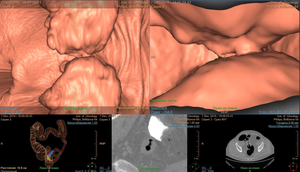

КТ- колонография – метод основан на раздувании отделов толстой кишки воздухом под контролем компьютерной томографии. Данная методика позволяет визуализировать стенозирующие опухоли кишки, непроходимы для колоноскопа при выполнении колоноскопии.